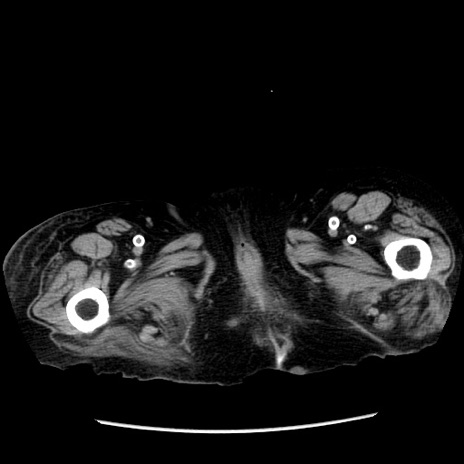

症例14(横断像)

【症例】 90歳代女性

【主訴】 腹痛・嘔吐

【現病歴】今朝から左側腹部痛を認めた。 経過観察していたが、嘔吐を認めたため来院。

【既往歴】 子宮癌術後

【身体所見】 意識清明、BP 127/54mmHg、P 98bpm Sp02 95%(RA)、BT 35.8°C、腹部平坦・軟腸ぜん動音聴取良好、右下腹部圧痛(+) 反跳痛なし

【データ】WBC 9800、CRP 0.46